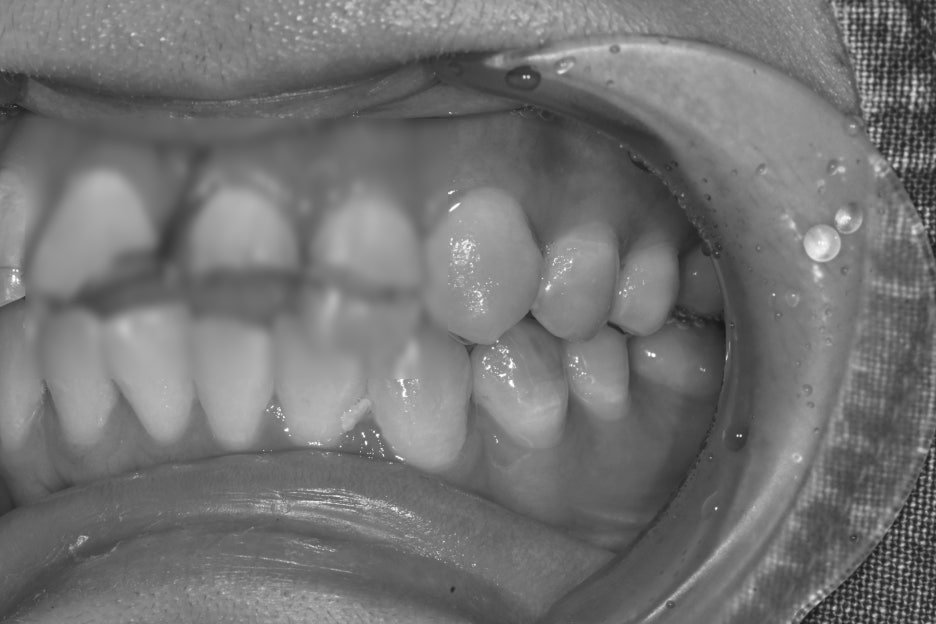

치료 전 후 사진

치료전, 치료후 사진